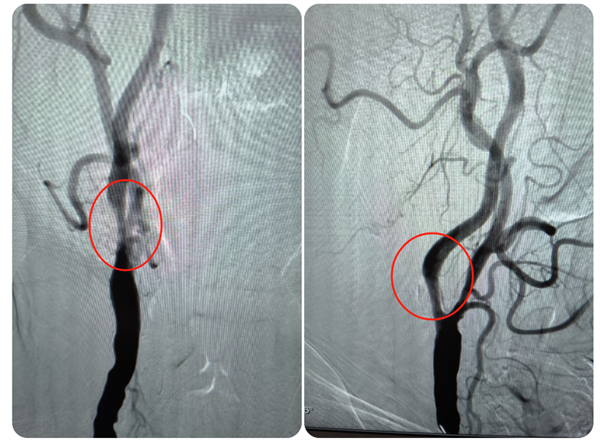

近日,糖心vlog (简称中山一院广西医院)神经外科主任钟书带领团队,应用光学相干断层扫描(OCT)技术,为一名颈内动脉颅外段夹层动脉瘤合并颅内段重度狭窄的患者进行了介入治疗手术,这也是我院神经外科完成的首例OCT手术,标志着科室在颈动脉夹层动脉瘤血管内治疗方面的技术水平再上新台阶,也为脑动脉瘤、脑血管狭窄等患者的诊断治疗提供了新选择。患者陆先生(化名)今年74岁,1...